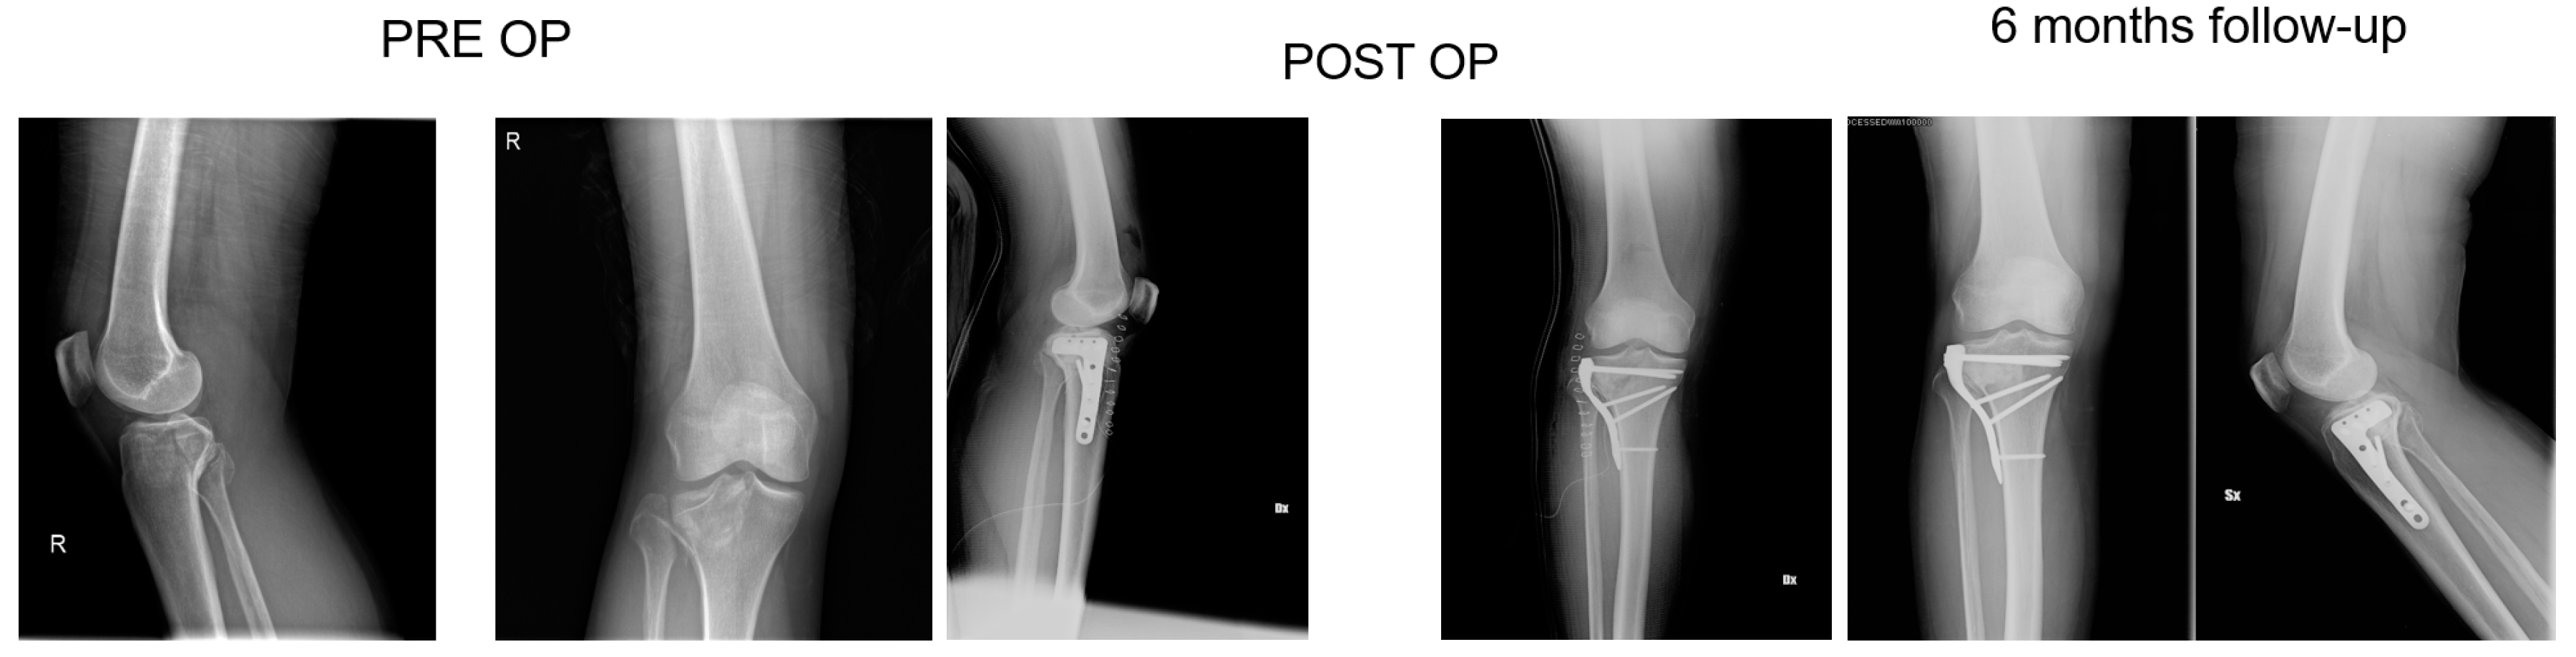

2.3. Surgical Technique and Rehabilitation

All patients had surgery within 48 hours from injury, after administration of spinal or general anaesthesia. A tourniquet was routinely positioned before starting surgical procedure; all patients were operated in a supine position, with injured leg in semi-flexion. Fractures were reduced through a percutaneous or open approach, depending on the cases; SB blocks, which size and shape were customised during surgery considering the features of bone defect for each singular patient, were positioned through a minimally invasive approach via the bony window exploited for reduction; finally, fixation of fracture line and implant were performed with screws and plates (see exemplificative Figure 1, Figure 2 and Figure 3). In one case fixation of the plateau fracture occurred through an arthroscopic approach. All the patients included in the study had identical post-operative regimen. Active knee mobilization and static quadriceps exercises were encouraged from the third day after surgery. Partial weight bearing was allowed at 4–6 weeks after surgery, and progressively increased to achieve full weight bearing at 12 weeks. Prophylaxis for thromboembolic events was obtained through administration of 4000 IU/day of low molecular weight heparin (LMWH) (enoxaparin), until full weight bearing was allowed.

Patients were clinically and radiologically assessed before surgery, at 2 weeks, and then at 1, 2, and 6 months, and 1 year after surgery. Same radiologist carried out the imaging, while evaluations were pooled by different clinicians. Clinical assessment consisted of a visual analogue scale (VAS) for the evaluation of pain, where patients were asked to report the level of pain during the day life activities; measurement of the range of motion (ROM) of the knee joint; and objective examination, intended to highlight possible alterations of surgical scar, vascular and nervous deficits, as well as infectious complications. Moreover, at 1-year follow-up Tegner Lysholm Knee Scoring Scale [21] and International Knee Document Committee 2000 (IKDC 2000) [22] questionnaires were administered during control visits, in order to evaluate patients’ subjective perception of knee function. One year after surgery, patients answered to the Short Form (36) Health Survey (SF-36) questionnaire, which scores the general physical and mental health on the basis of eight scales each ranging from 0 to 100 [23]. Radiological assessment contemplated the acquisition of anteroposterior and lateral projections radiographs at each follow-up. Images were examined in order to evaluate various features of healing process, like callus formation and maintenance of fracture reduction; as well as to detect the presence of possible malalignment, pseudo-arthrosis, bone non-unions, and articular surface depression or widening (see exemplificative Figure 1, Figure 2 and Figure 3).

At six months, X-rays images showed that all 34 fractures displayed a good consolidation rate, as confirmed by radiological reports. In particular, radiolucency of the xenografts was assessed [20], which became progressively more similar to that of the surrounding healthy bone tissue (see exemplificative Figure 1, Figure 2 and Figure 3 and comparative images in Figure 4).

Comparison with the current literature is challenging, due to the lack of standardised follow-up protocols and differences in quantitative assessment of outcomes among the studies. However, the implant of SB in our series resulted in a standard return to knee mobilisation, as highlighted by the mean ROM at last follow-up and the return to partial weight bearing at 4–6 weeks. We also described no complications, like infections and joint subsidence, if compared to similar studies present in the medical literature [31]. Radiological follow-up did not show diastasis or depressions of tibial articular surface excluding the incomplete subchondral reductions documented at the first post op X-ray, which means that mechanical properties of SB were adequate for high and complex forces which the plateau commonly undergoes. At each follow-up, the radiolucency of implants was progressively more similar to radiolucency of the surrounding bone (see exemplificative Figure 1 and Figure 2). We interpreted this evidence as supporting the thesis that SB would have been able to integrate with autologous bone tissue, favouring deposition of new bone matrix within an ongoing remodelling process: indeed, there is a clear morphological pattern on the evolution of the standard X-Ray imaging series over time which shows the substitution of the grafted material with a more homogeneous signal in the area of graft implant. As already demonstrated, the progressive remodelling together with an increase of the mineral signal cannot be dependent on the active remodelling of the graft per se given it is a decellularized matrix. Therefore, the increase in the density over time depends on novel mineral matrix apposition likely induced by the graft, as previously shown both in vivo and in vitro [7,20].

Figure 3. 68 years old patient, X-rays: preoperative, postoperative and control at 2 months follow up of a Shatzker type 2 fracture, AO 41 B1.3.